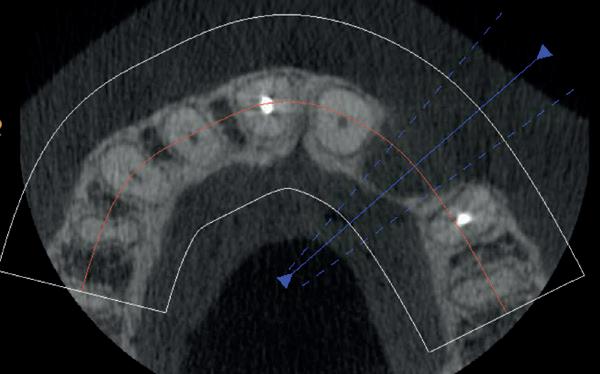

Na vier maanden wordt er een CBCT gemaakt om het botvolume te kunnen beoordelen en een digitale planning te kunnen maken voor het plaatsen van het implantaat. Tevens wordt de stabiliteit van de botpieken op het buurelementen bekeken (foto 15 en 16).

Tijdens het verwijderen van het membraan is het botvolume klinisch waarneembaar en blijkt dat er voldoende bot is om het implantaat te kunnen plaat-